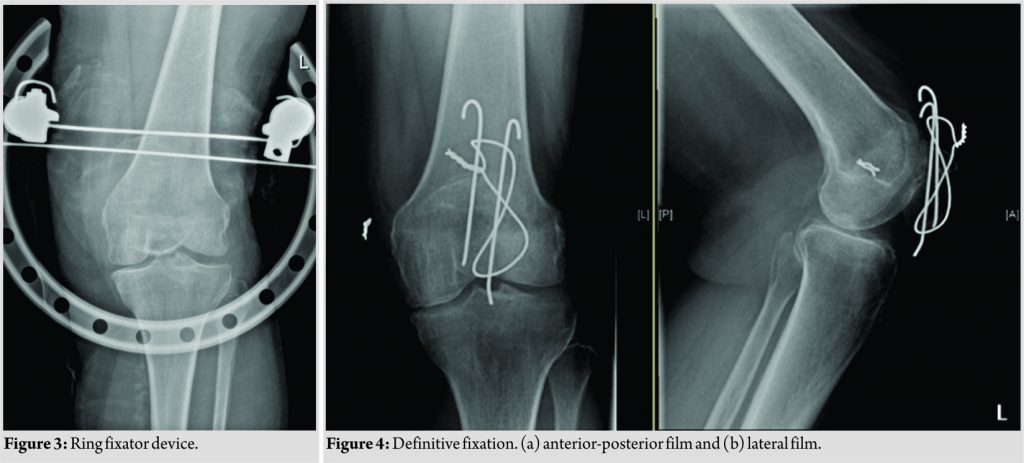

A decision was made to proceed with a two-staged reconstruction of the extensor mechanism. The first stage involved application of skeletal traction on the proximal fragment (Fig. 2 and 3). Due to the patient’s poor bone quality, the decision was made to apply tension wire skeletal traction using a ring fixator device with one wire passing through the bone and a second wire through the quadriceps tendon (Fig. 4). Following this, progressive traction was applied from 5 to 12 lbs over a period of 10 days. Once adequate mobilization of the proximal patella fragment was achieved, we proceeded to the second stage which involved a conventional tension band wiring to achieve definitive fixation (Fig. 4). At 1-year follow-up, the patient had achieved full independent mobility. She demonstrated full extension of the knee joint with preserved active SLR. She was subsequently discharged from follow-up.